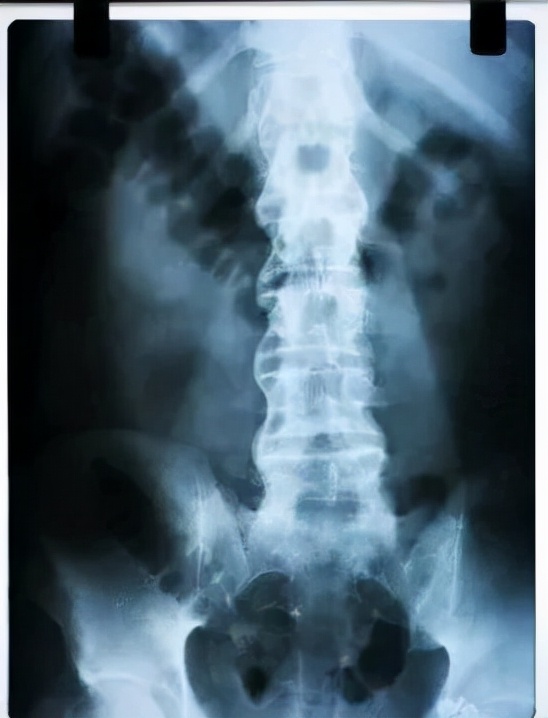

人類在20世紀30年代才認識到,幾乎所有強直性脊柱炎患者都存在X線骶髂關節炎,從此,X線骶髂關節炎成為該病診斷的必要條件。

但後來發現部分患者X光檢查但卻沒發現骶髂關節破壞,但在磁共振(MR)下卻能看到活動性炎症徵象。

2009、2011年,國際脊柱關節炎評估組又提出了中軸型脊柱關節炎,包括強直性脊柱炎、放射學陰性中軸型脊柱關節炎,它們在臨床中表現為多種症狀,常難以識別,導致診斷延遲、漏診或誤診。